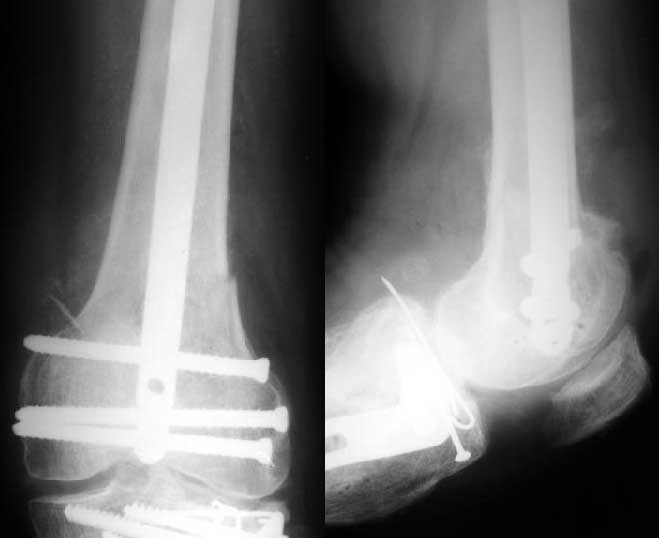

Sorry but I've just prepared postop images - attached. A solid 13 mm nail was used. A few degrees of recurvation appears to be which i missed on image intensifier. I'm still uncertain about

advantages/disadvantages of ante/retrograde nailing for such fractures.